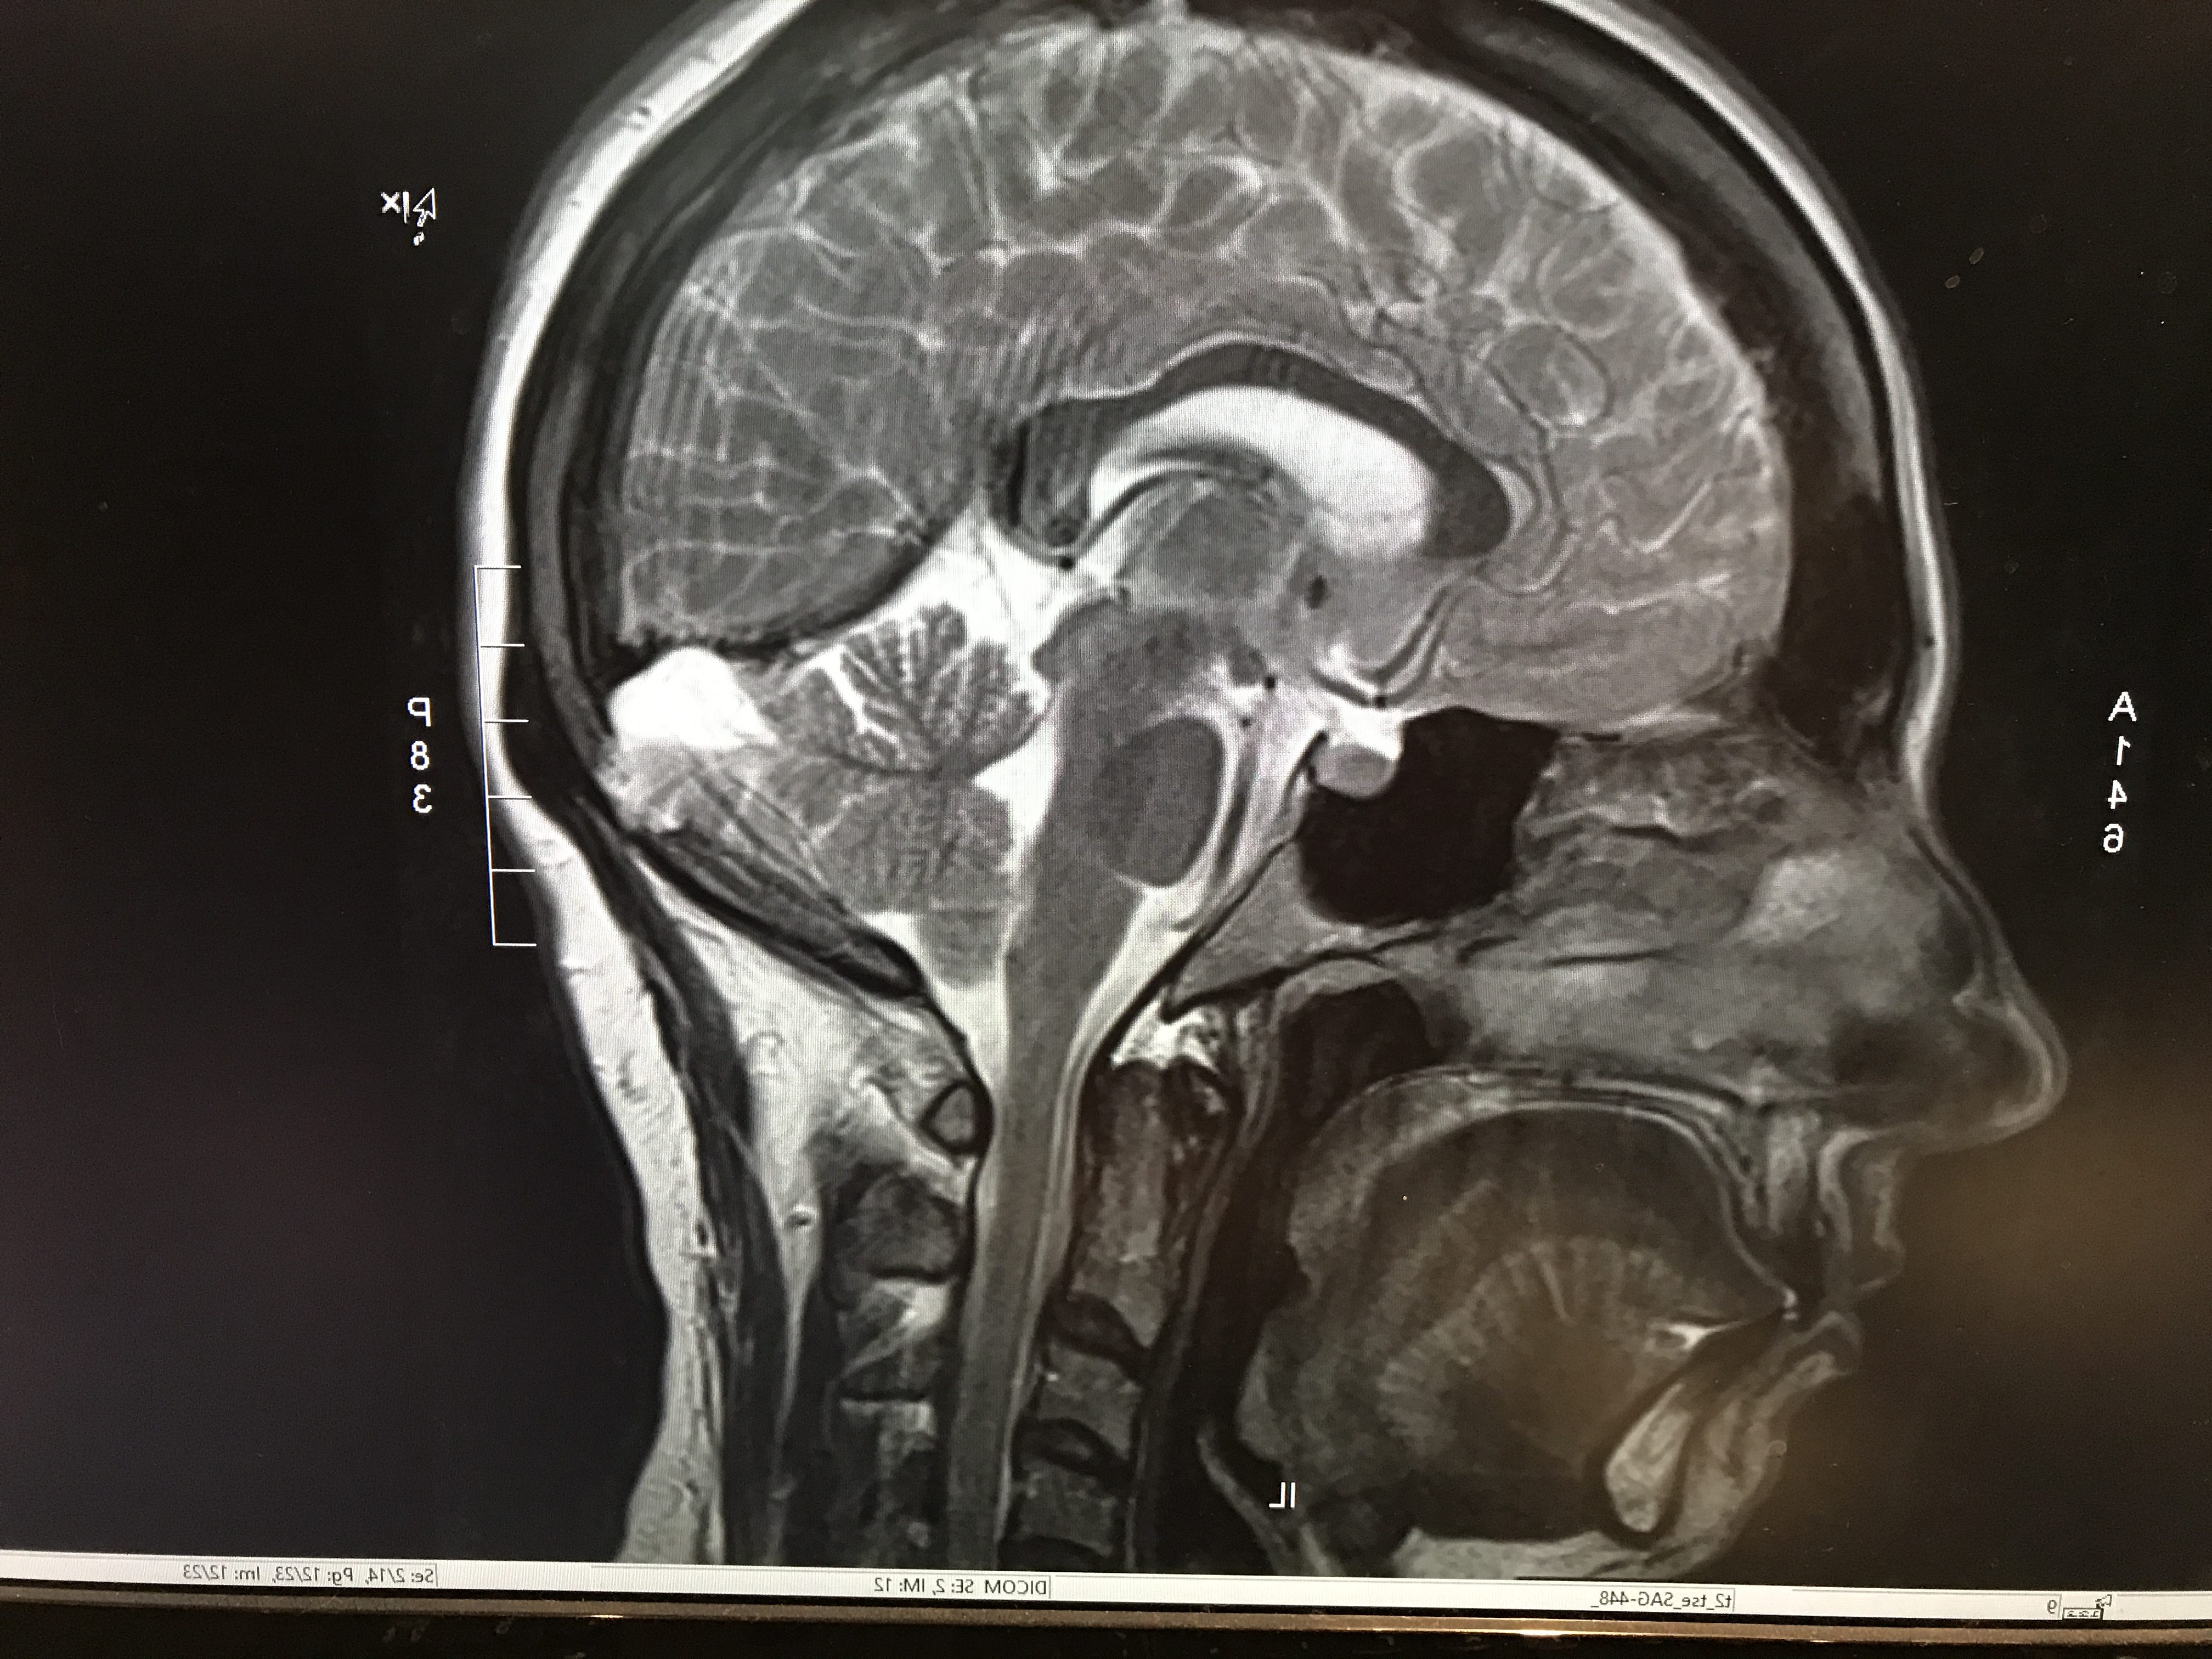

J’ai pu ramener le CD avec moi, et le regarder tout de suite… j’ai failli ne pas le faire. Mais j’ai assez de tête sur les épaules pour savoir que je n’ai pas les connaissances pour tout comprendre, donc je ne m’affolais de rien de ce que je voyais, je pouvais juste tenter de reconnaître les structures et m’émerveiller de la beauté des images.

En attendant, mon endocrinologue a voulu avoir les images de l’IRM de juillet pour faire faire une 2e analyse (un 2e avis, quoi), afin de confirmer qu’il n’y avait rien d’anormal en juillet… ce qui ne voudrait malheureusement pas dire qu’il n’y a rien d’anormal maintenant.